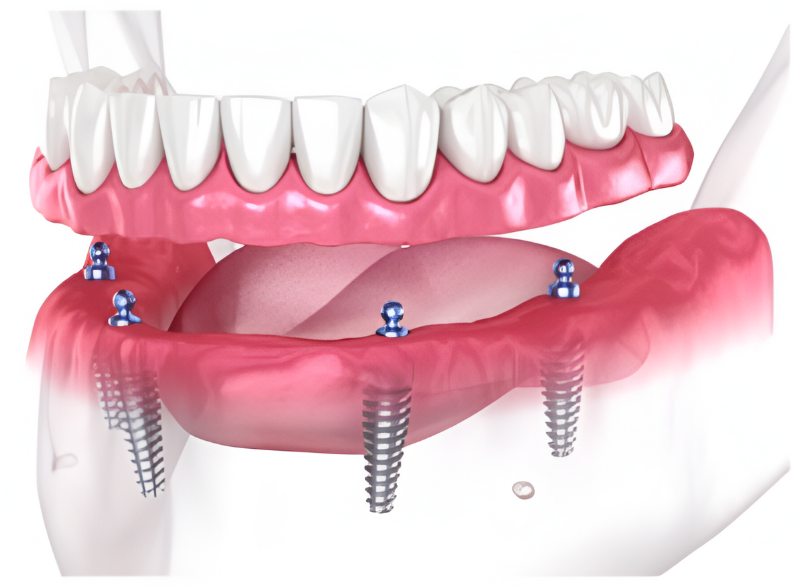

Every single dental implant consists of three parts - the implant, the abutment, & the crown. The implant is made of medical grade titanium. This part is surgically placed into the patient’s jaw bone and left to heal for 4-6 months afterwards.

This implant piece acts as the foundation for the rest of the tooth. Once the bone around the site has healed, the abutment and crown are placed on top of the implant. The end result is a beautiful, natural-looking new tooth!

Few people will ever be able to tell the difference between your implants and your real teeth.